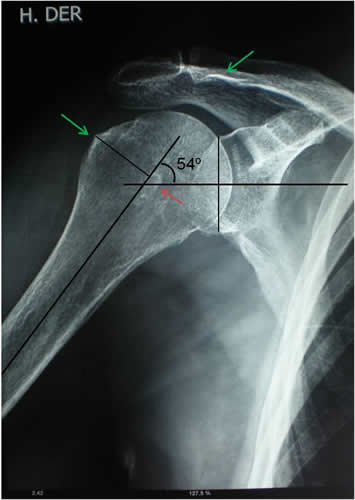

- Paciente: CP 76 años, femenino

- Motivo de consulta: Dolor e impotencia funcional en hombro derecho. Capsulitis adhesiva. Síndrome de Impacto.

- Inicio de tratamiento: Enero de 2010

- Fin del tto.: Marzo de 2010

- Total de sesiones realizadas: 8 sesiones